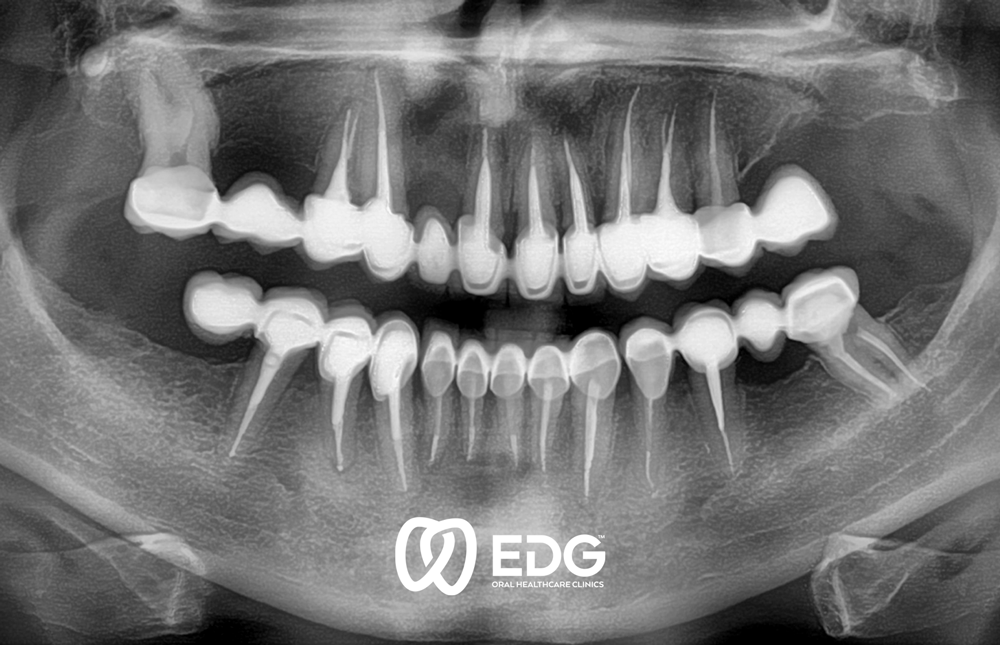

The loss of a tooth can be due to various reasons: caries, periodontitis or injuries and accidents. We offer our patients up-to-date care which brings in line aesthetic and functional standards and individual requirements. We insist on the inseparable connection between the form and function of dental prosthetics. Only functionally good work leads to good aesthetic results. For the selection and manufacture of the dental prosthesis, objective criteria play a part as well the patient type and the patient’s age. The complex prosthodontic reconstruction of the dentition requires a precise and extensive diagnosis before reconstructive measures can be started. To do this, a thorough medical anamnesis is necessary, as well as radiodiagnostics and the use of modern methods to exactly determine the position of the teeth and the movement of the temporomandibular (jaw) joint. For prosthodontic restoration, we use modern crown and bridge technology, partial and full prostheses and implants.

Prosthodontic restoration must meet functional as well as aesthetic requirements. We make a point of having the prosthetics fit into the remaining dentition without being distracting. At the same time, our aesthetic demands on prosthetic care are very high.